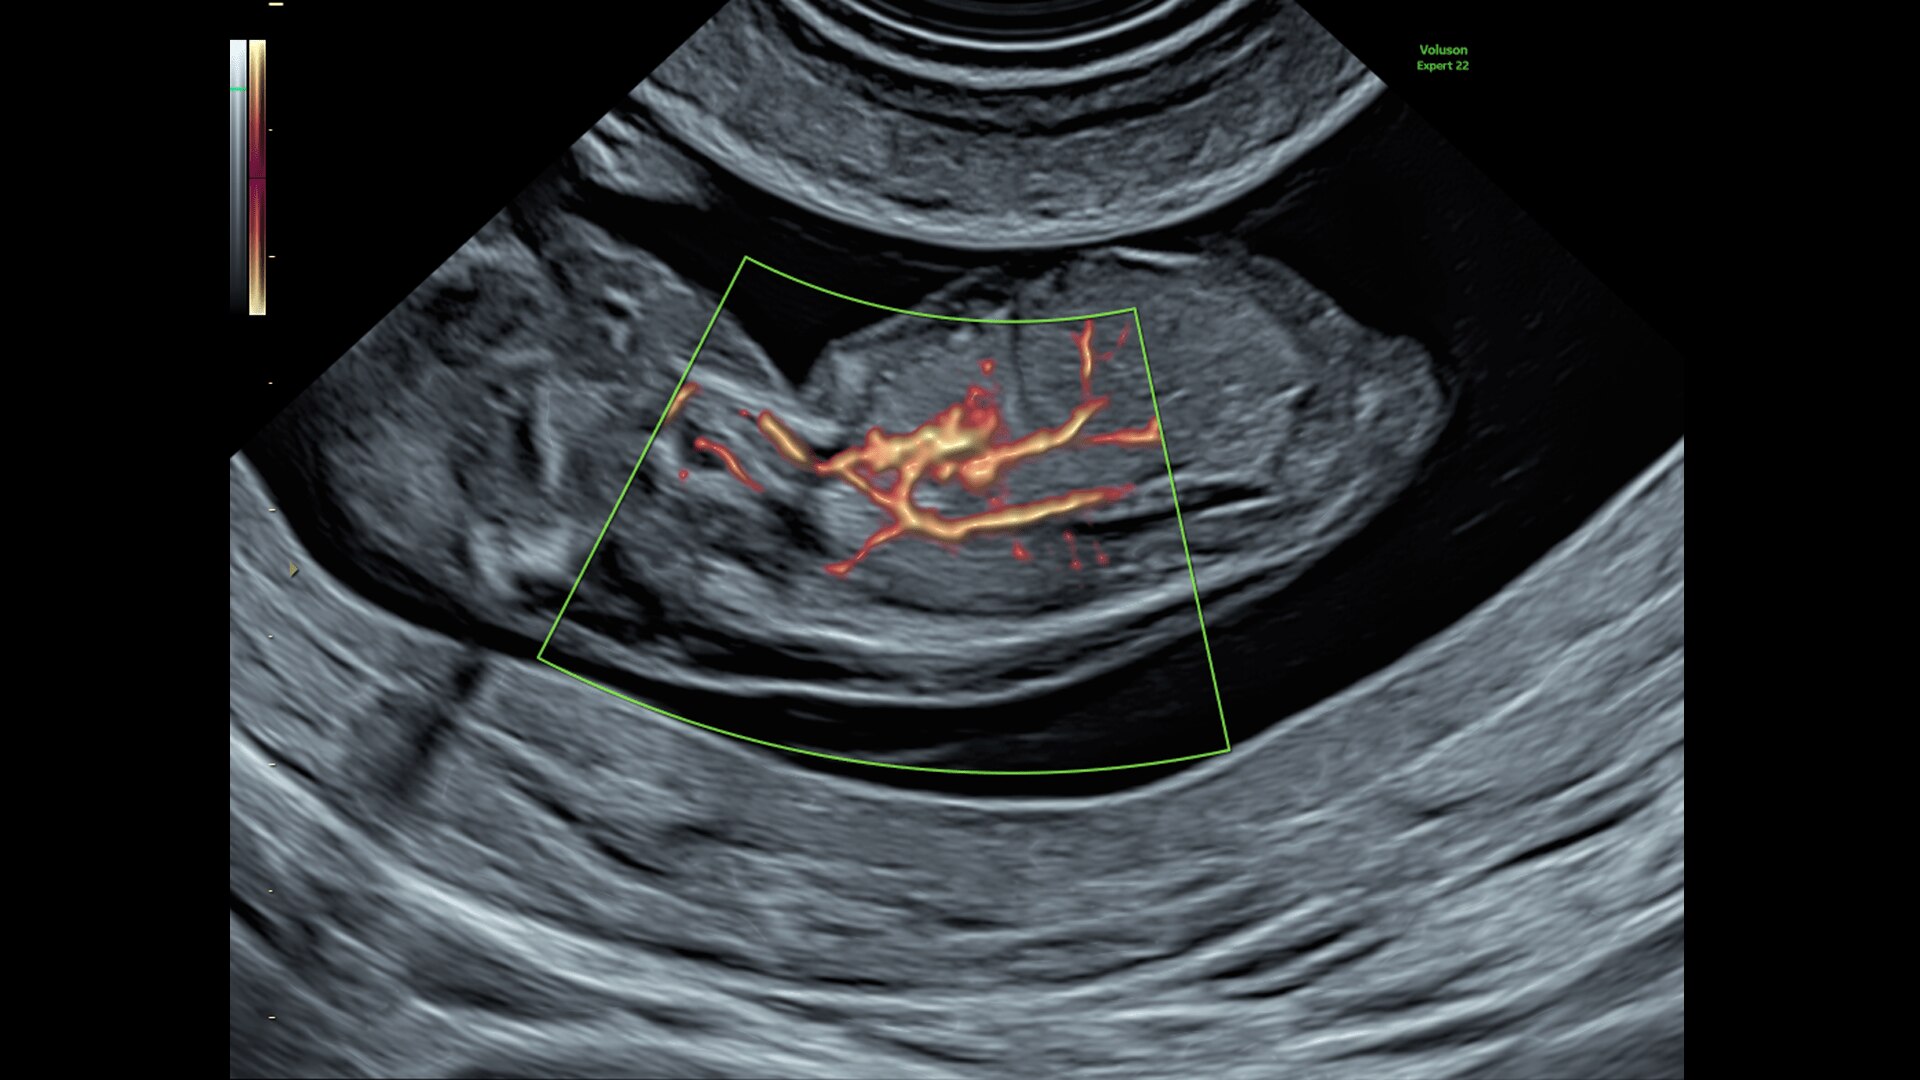

FETAL HEART EVALUATION

Get to the Heart of the Matter

Identifying fetal cardiac abnormalities earlier means you can intervene sooner, plan for delivery, and potentially improve outcomes. The Voluson Expert 22 provides a full solution of progressive tools, to help distinguish the tiniest structures with stunning clarity to provide patient answers faster.